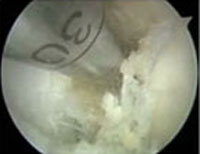

- The orthopaedic surgeon inspects the Knee and removes the remains of the old ACL using an arthroscopic shaver.

- The graft which gets used for reconstruction, is harvested and prepared for the replacement. Usually the patellar tendon or the Semitendinosis and Gracilis tendon autografts are used in athletes.